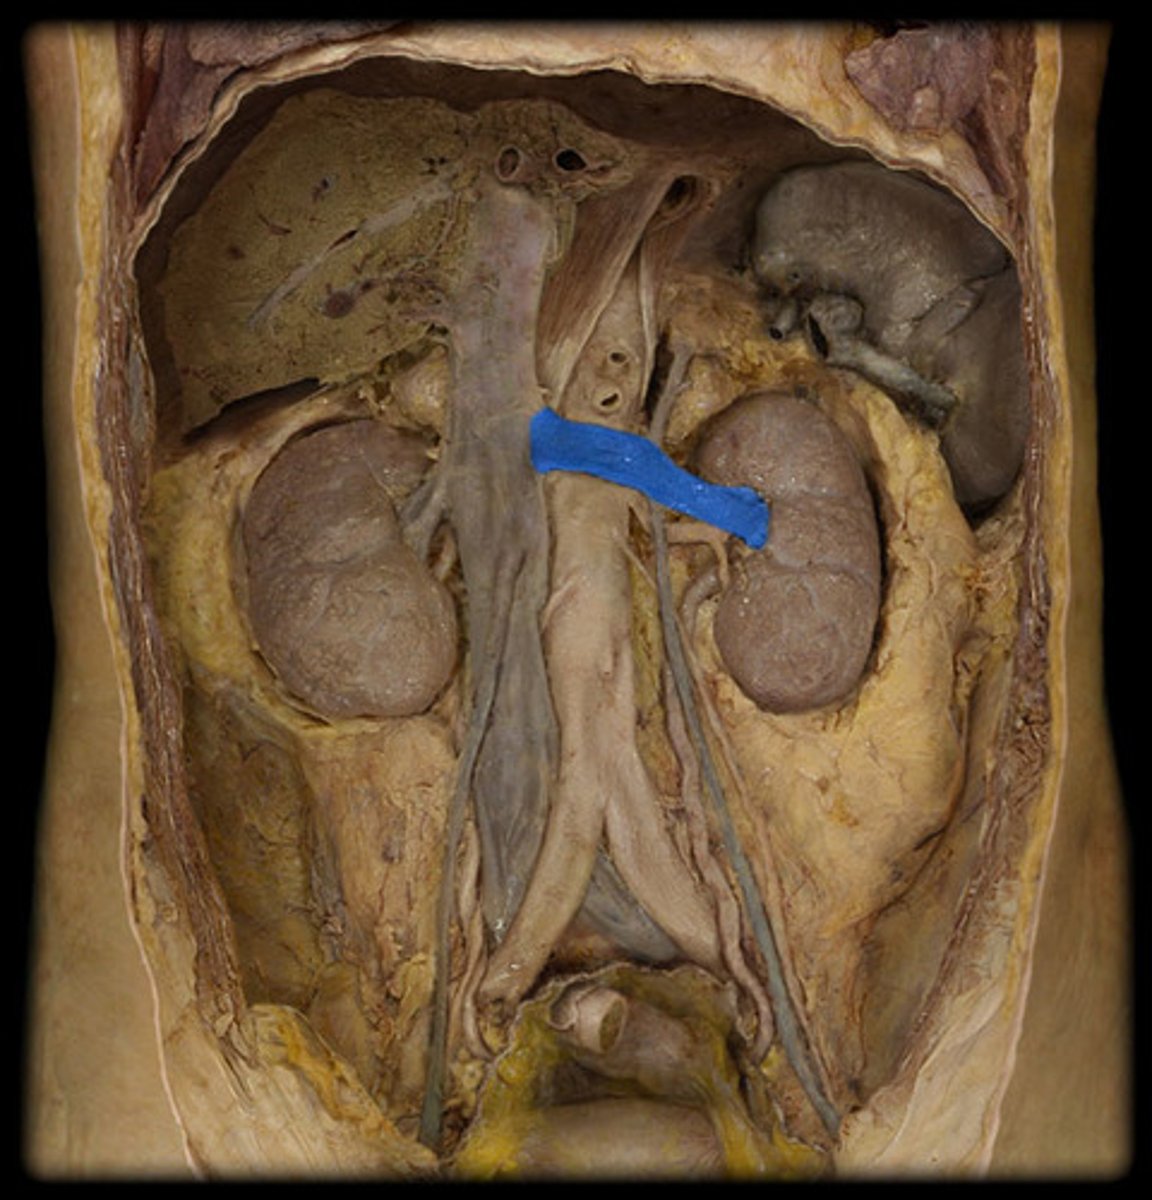

What is this?

Renal vein

Renal artery

Renal pelvis

Renal capsule

Renal cortex

Renal columns

Renal medulla includes what?

Renal pyramids

Renal papillae

Minor calyx

Major calyx